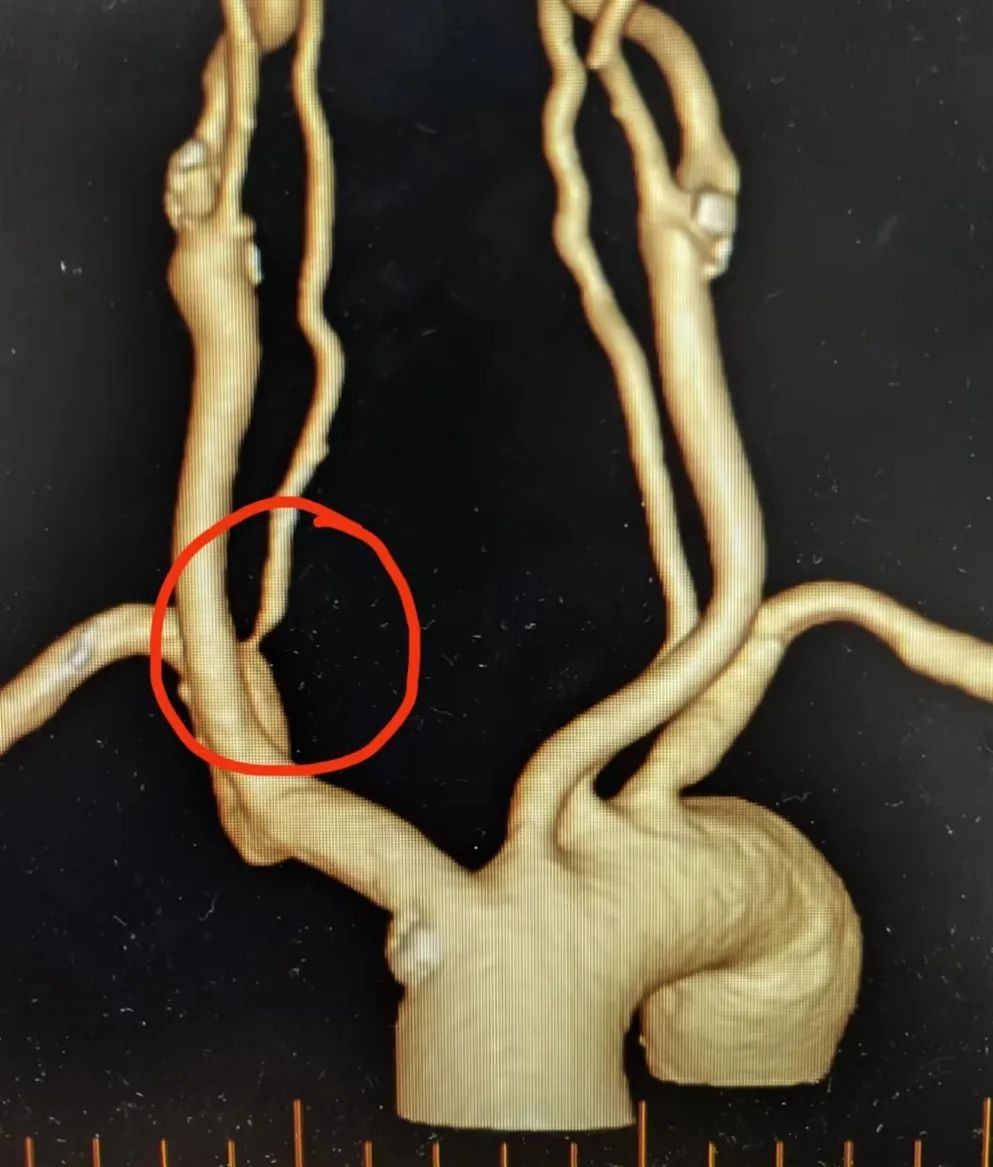

本次患者为中年男性,间断性头晕数年,既往有糖尿病病史,头颈部CT血管造影检查(简称CTA)显示右椎动脉重度狭窄。

术前CTA显示右椎动脉重度狭窄